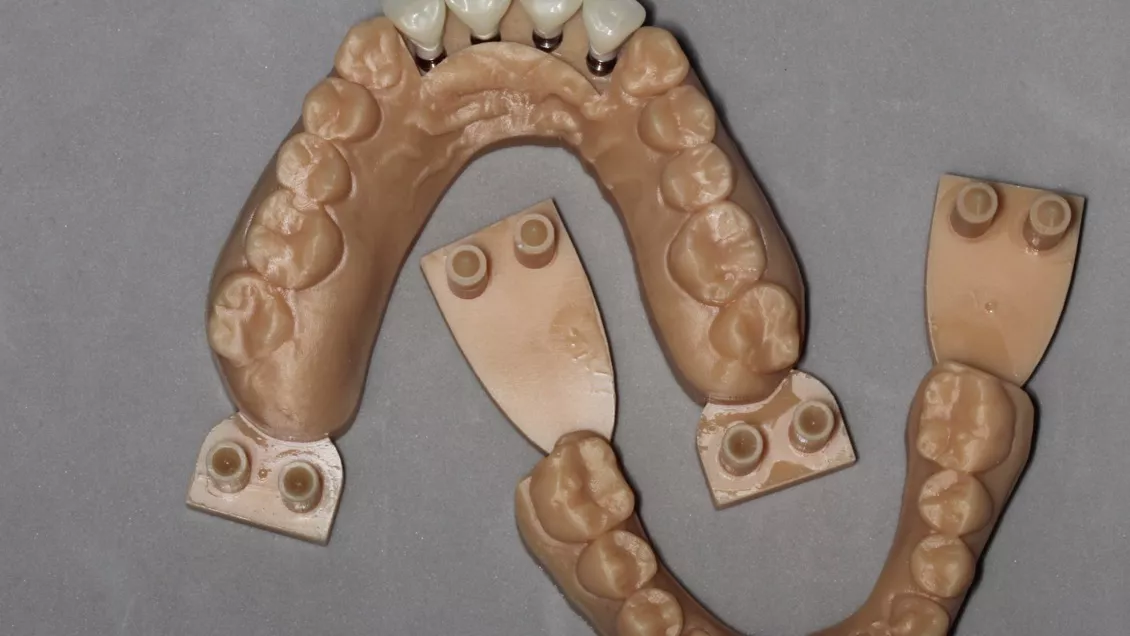

Guided rehabilitation with implant in upper incisors region, after loss due to root resorption